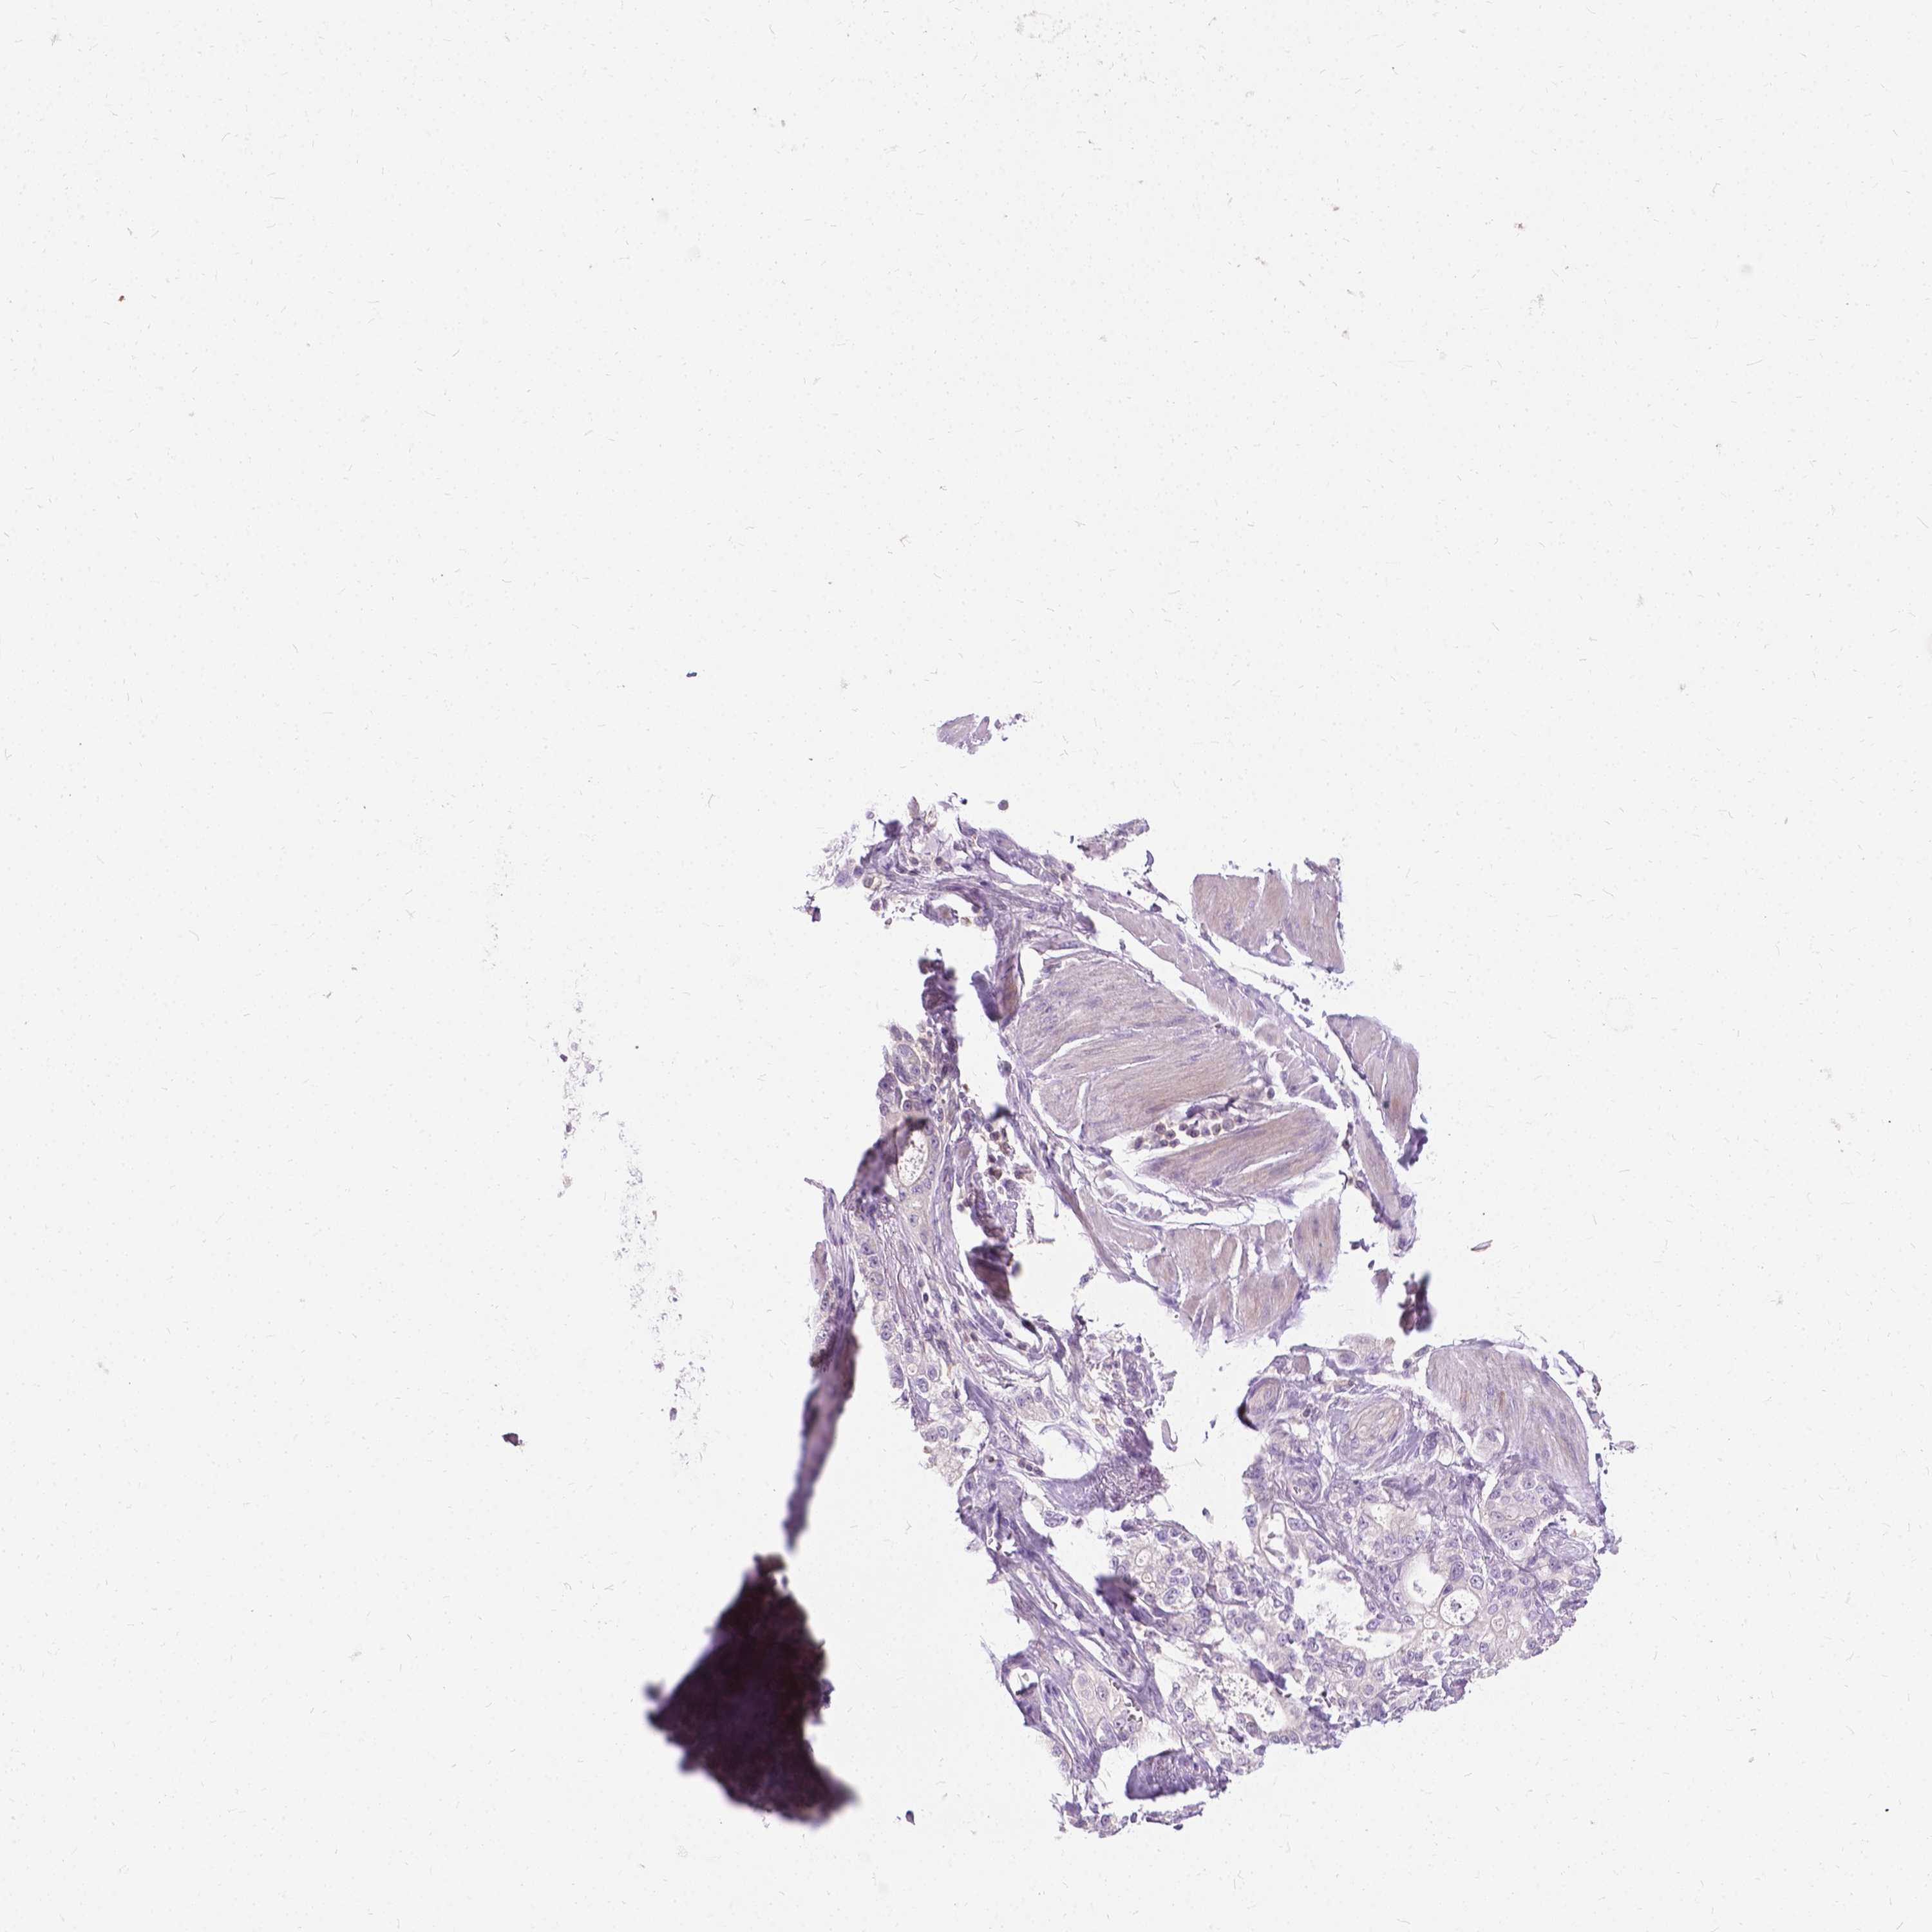

STOMACH CANCER - Protein expressioni

A mouse-over function shows sample information and annotation data. Click on an image to view it in a full screen mode. Samples can be filtered based on level of antibody staining by selecting one or several of the following categories: high, medium, low and not detected. The assay and annotation is described here.

Note that samples used for immunohistochemistry by the Human Protein Atlas do not correspond to samples in the TCGA dataset.

Antibody stainingi

Antibody staining in the annotated cell types in the current human tissue is reported as not detected, low, medium, or high, based on conventional immunohistochemistry profiling in selected tissues. This score is based on the combination of the staining intensity and fraction of stained cells.

Each image is clickable and will lead to virtual microscopy that enables deeper exploration of all samples and also displays staining intensity scores, fraction scores and subcellular localization as well as patient and tissue information for each sample.

Antibody HPA070314

Staining

High

Medium

Low

Not detected

Intensity

Strong

Moderate

Weak

Negative

Quantity

>75%

75%-25%

<25%

None

Location

Nuclear

Cytoplasmic/membranous

Cytoplasmic/membranous,nuclear

Adenocarcinoma, NOS